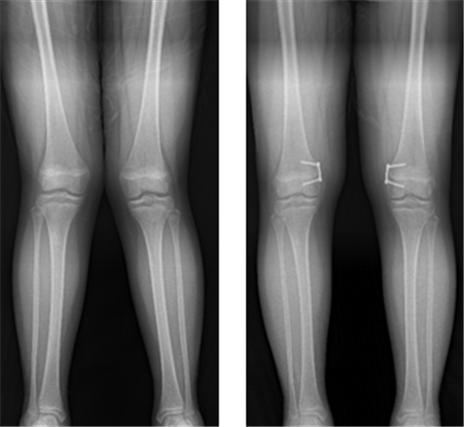

분당서울대병원 정형외과 성기혁 교수팀은 오다리, 엑스자 다리 치료를 위해 금속판을 이용한 반성장판 유합술을 받은 소아 환자를 대상으로 교정 이후 발생하는 반발현상(재발) 및 위험인자를 분석한 결과, 이같이 확인됐다고 31일 밝혔다.

반성장판 유합술은 O자형(내반슬), X자형(외반슬) 다리로 병적인 변형이 있는 소아에 대해 8자 모양의 금속판을 이용해 일시적으로 한쪽 성장판의 기능을 억제해 성장하면서 변형이 교정될 수 있도록 하는 수술 방법이다. 교정이 완료되면 성장이 재개되기 때문에 상대적으로 더 어린 나이에 시행이 가능하며, 효과적인 교정을 기대할 수 있다.

그러나 지나치게 이른 나이에 수술하면 오히려 재발 위험이 높아질 수 있는 것으로 나타났다. 연구팀은 반성장판 유합술을 시행한 94명의 성장판을 대상으로 재발위험인자를 알아보기 위한 연구를 진행했다. 이들의 평균 나이는 11세였으며, 변형이 교정돼 금속판을 제거한 후 5도 이상의 변형이 재발한 경우 재발군으로, 그렇지 않은 경우를 비재발군으로 분류했다.

그 결과 41명이 재발군, 53명이 비재발군에 속했다. 재발군의 수술 시 평균 나이는 10.2세로 비재발군의 11.7세에 비해 유의미하게 연령이 낮았다. 또 재발군의 교정속도는 1년간 10.2도로, 비재발군의 교정속도가 1년간 6.5도인 것에 비해 유의미하게 빨랐다.

회귀분석 결과, 변형의 교정속도가 수술 후 변형 재발의 위험인자인 것으로 나타났으며, 교정 속도가 1년에 1도 증가할수록 재발 위험은 1.2배 증가했다. 아울러 재발군과 비재발군을 나누는 분기점은 약 7도였다. 따라서 교정속도가 7도 이상인 환자의 경우 금속판 제거 후 증상이 재발할 위험이 높아진다는 것을 확인했다.

성 교수는 "소아에서 오다리나 엑스자 다리는 금속판을 이용한 반성장판 유합술로 교정할 수 있지만, 교정속도가 빠른 소아 환자, 그중에서도 특히 1년에 7도 이상인 환자는 교정이 된 후 금속판을 제거했을 때 재발 현상을 보일 위험이 높으므로 추가적인 관찰이 필요하다"며 "특히 10세 이하로 너무 어린 나이에 수술하는 경우는 재발 위험이 커지므로 전문의와 상담을 통해 적절한 시기에 수술을 받는 것을 권한다"고 말했다.